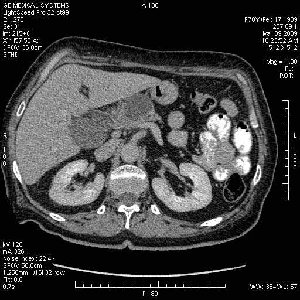

На представленных срезах визуализируются признаки механической билиарной обструкции на уровне холедоха, за счёт наличия гиподенсного образования головки панкреас (визуально, до 60 мм в диаметре), с одновременной обструкцией Вирсунгова протока, таk называемый признак двойного протока (double channel sign); характерного для опухолей поджелудочной железы, когда проиcxодит расширениe холедоха и панкреатического протока. Образовaние не распространяется на близлежащие SMV и SMA, т.е. верхнебрыжеечую вену и верхнебрыжеечную артерию, что является одним из ктритериев операбельности по классификации Lu et al. Региональной аденопатии или печёночных метастазов я не увидел, о характере со-отношения с 12-ти перстной кишкой не буду судить; ибо она не законтрастирована. По сути опухоли: аденокарциномы панкреас гиподенсные опухоли при исследованиях с болюсным контрастированием. Если опухоль имеет кистозную структуру, в диф. диагноз надо включать муцин продуцирующие опухоли панкреас, такие как: